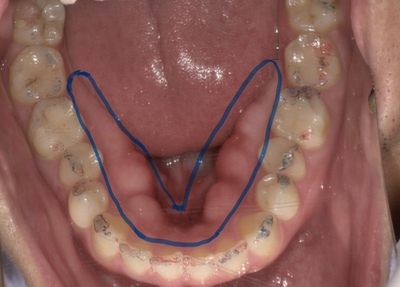

歯科臨床では、食いしばりなどが原因で長期間にわたり強い咬合圧が加わることで、顎の骨が盛り上がる「骨隆起(こつりゅうき)」が確認されることがあります。(下顎の内側に見られることが多いです。)

骨は持続的な力に適応する組織であり、骨隆起は“力の履歴”を示す所見の一つと考えられています。